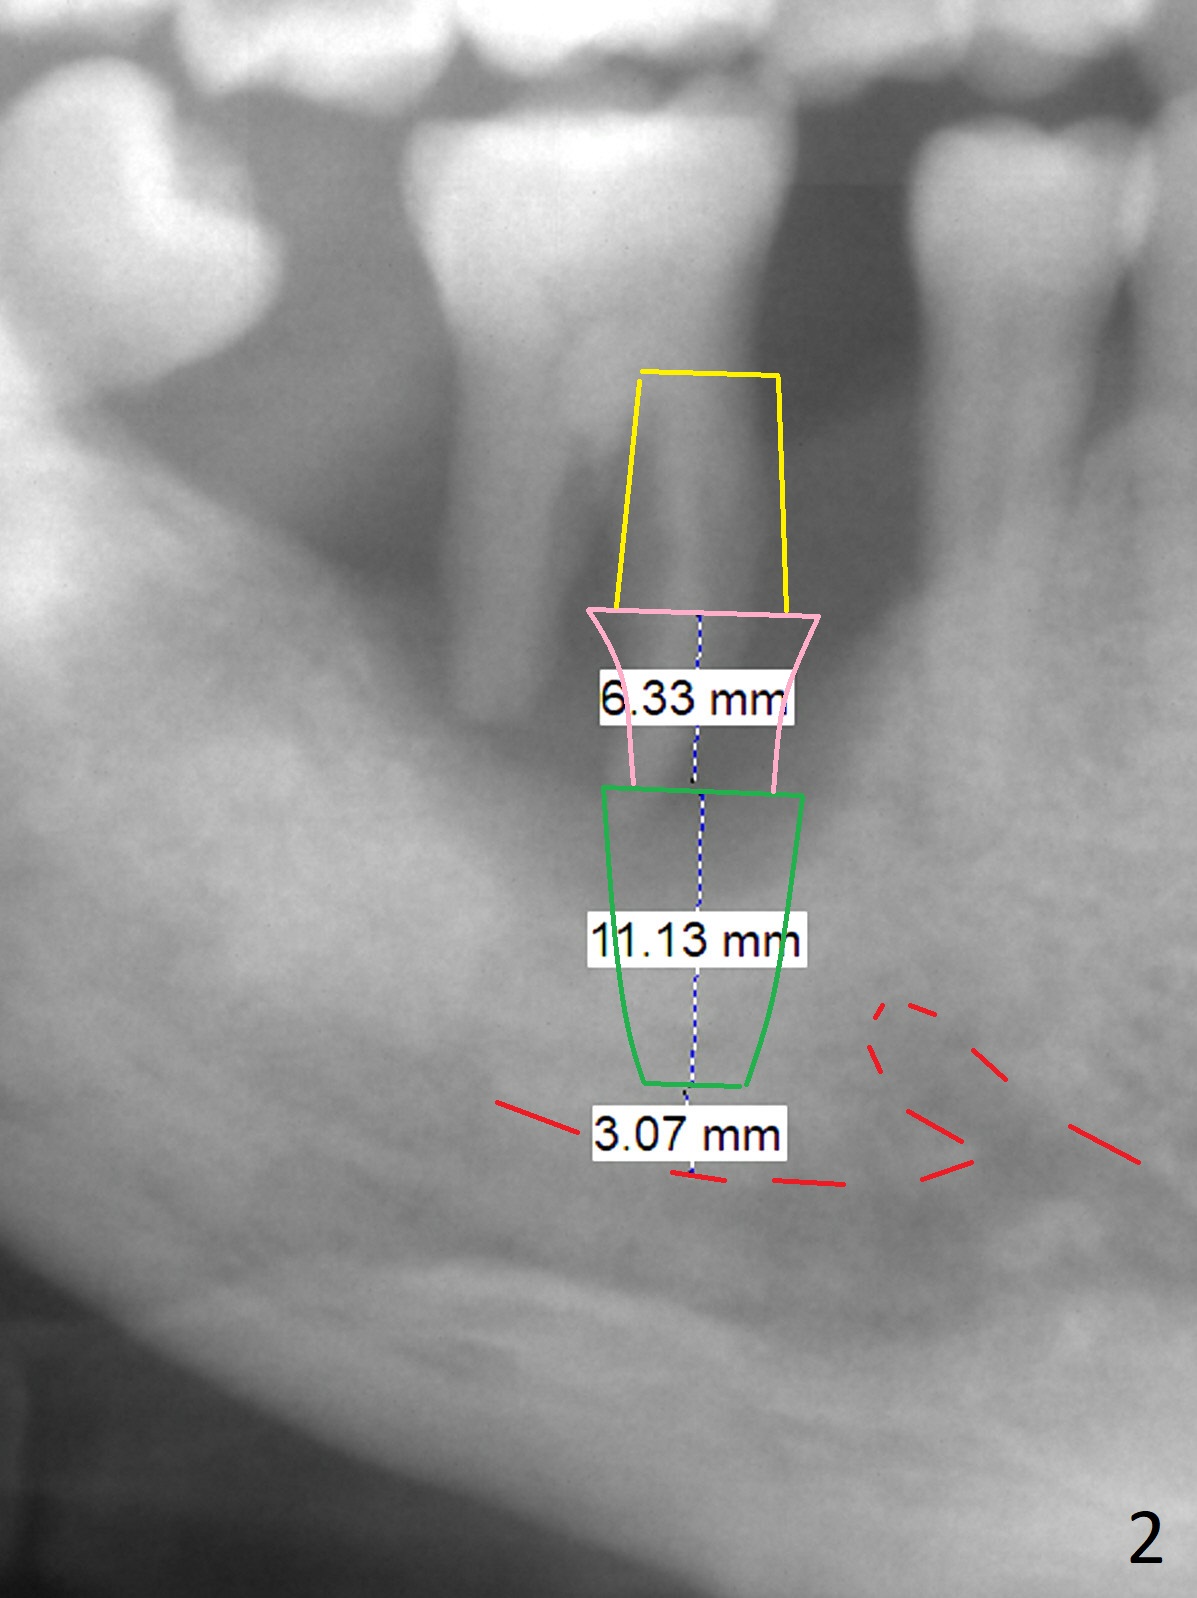

Drifting Molar A 57-year-old man has advanced periodontitis with bruxism. The mobile teeth #13 and 30 are his main concern (Fig.1). The tooth #30 has shifted distally. An implant will be placed in the mesial socket, if present. Due to severe bone loss, a 7 mm long abutment with 6 mm cuff is most likely to be used (Fig.2). Since the socket is huge, prepare large piece of gauze for hemostasis. Osteotomy should be initiated as buccal as possible, as the Inferior Alveolar Canal is near the lingual plate at the 1st molar. Prepare Sinus Master Kit. Why? Always take PA after initial drill to avoid violating the Canal. It may be ok to see the overlapping between the parallel pin and the Canal. Do not administer the Inferior Alveolar nerve block. Return to